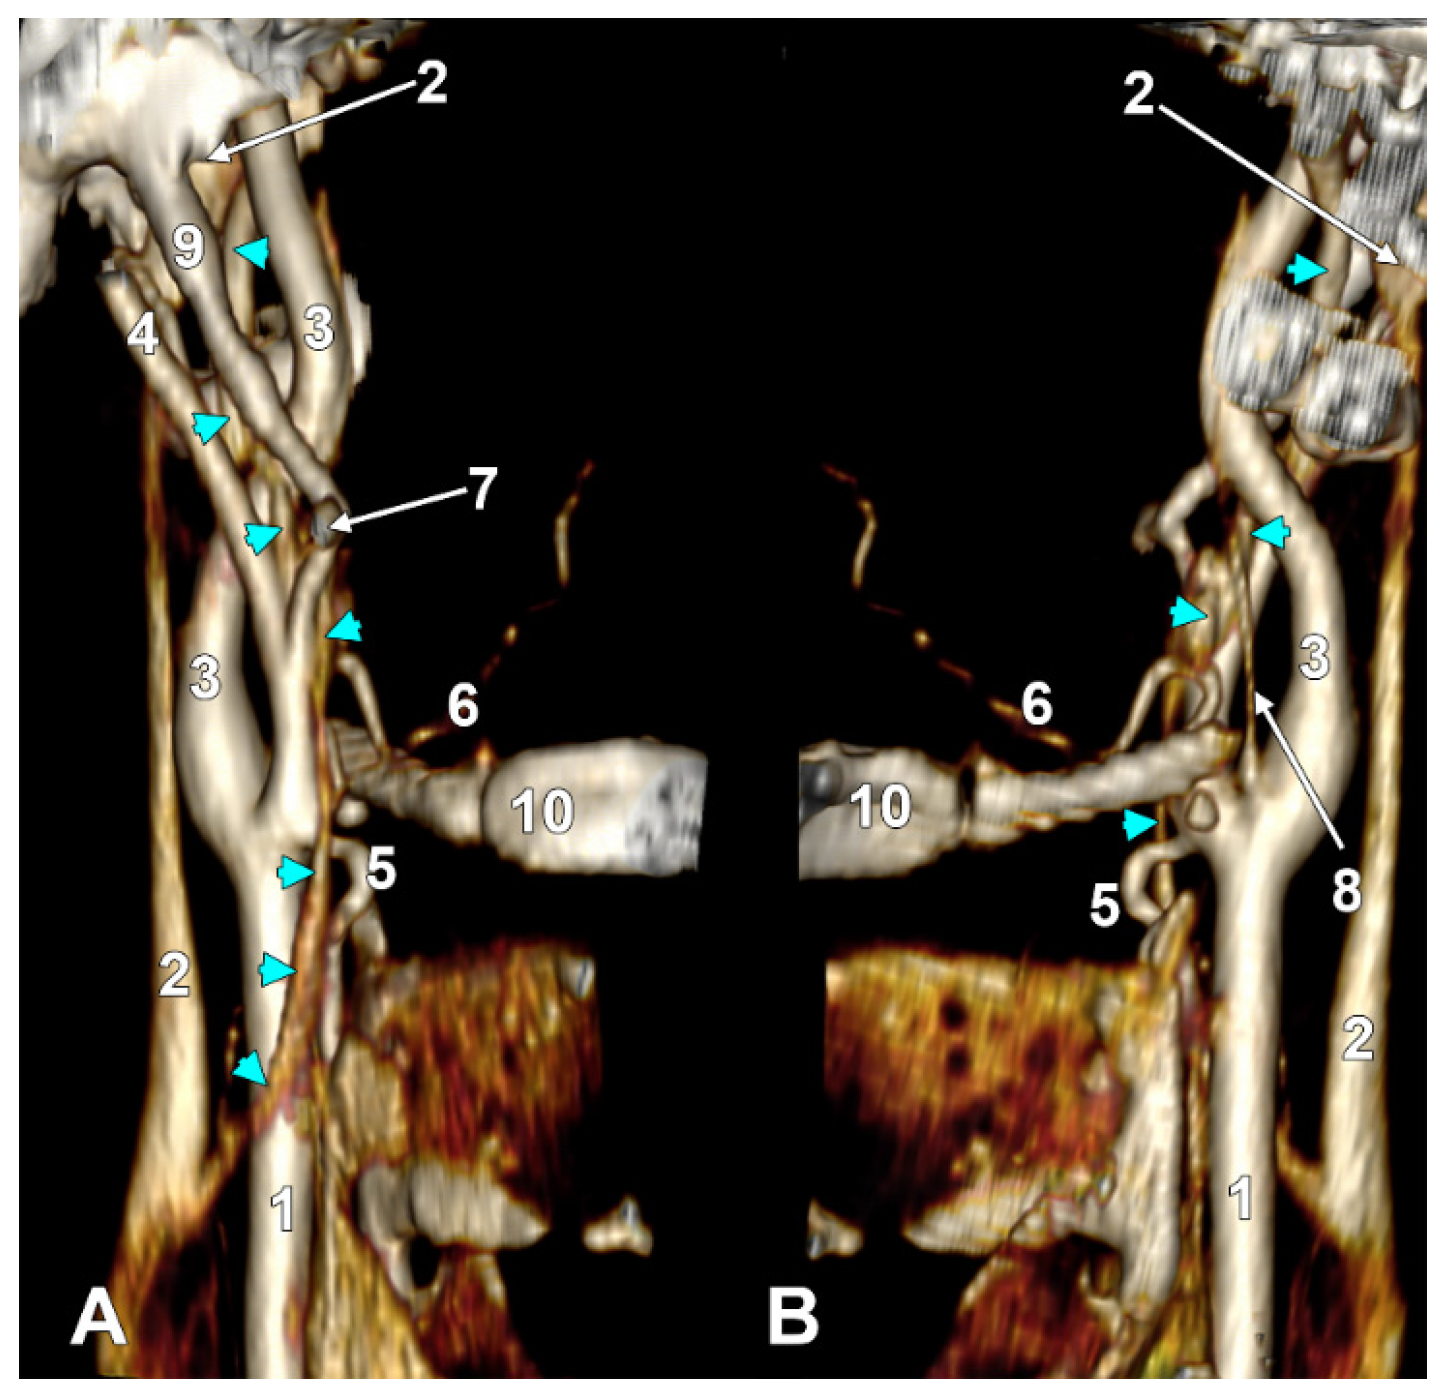

Figure 11. Type V ascending pharyngeal artery originating from the carotid bifurcation. Superior laryngeal artery with suprahyoid origin. Three-dimensional rendering. Left side. (A) Lateral view. (B) Medial view. 1. Common carotid artery; 2. internal carotid artery; 3. external carotid artery; 4. styloid process; 5. superior thyroid artery; 6. superior laryngeal artery; 7. ascending pharyngeal artery; 8. occipital artery; 9. lingual artery; 10. facial artery; 11. maxillary artery; 12. superficial temporal artery; 13. transverse facial artery; 14. thyroid cartilage; 15. greater hyoid horn; 16. sternocleidomastoid branch; 17. descending branch; 18. posterior branch.

3.7. The S40 Type of the Origin of the External Carotid Artery’s Branches

In one of the studied cases, we found, on the left side, an unexpected arterial variant, corresponding to the type S40 (STA/APA from the CB, OA/SCM br.-LA). The CB was subgonial, 1.82 cm posterosuperior to the hyoid tubercle. From the medial aspect of the CB, the left two branches were as follows: one descending—the STA, and the other ascending—the APA (Figure 11). The ECA and ICA made an angle of 62.39°, opened superiorly. The initial segment of the ECA, 1.53 cm long, was directed anterosuperiorly, and then the ECA made an angle of 118.85°, opening posteriorly to further continue with the retromandibular course. At 6 mm distal to the origin of the STA and APA, the LA, OA, and a SCM branch originated from the ECA at the same level. The SCM branch originated from the lateral wall of the ECA, the AO from the inferomedial wall of the ECA, and the OA from the superolateral wall of the ECA. At 0.93 cm distally to the origin of the latter, the FA originated from the ECA.

The SCM branch traversed the venous fork between the common facial vein and the IJV, deep into the sternocleidomastoid.

The left STA had a 1.39 cm suprahyoid segment from which, 4 mm superior to the hyoid tubercle, the superior laryngeal artery arose. The latter described an ‘S’-shaped course, passing at 4.2 mm medial to the hyoid tubercle and then returning laterally, applied to the lateral aspect of the thyrohyoid membrane. The left ECA trifurcated into the maxillary, superficial temporal, and transverse facial arteries.